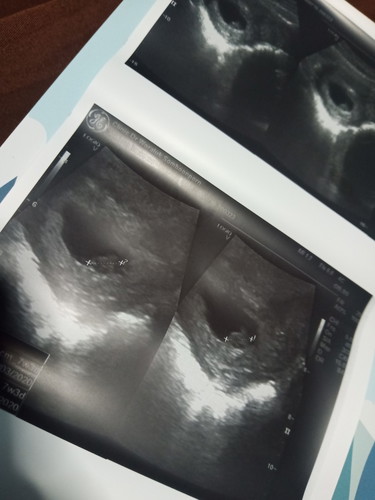

วันนี้คุณหมอนัดตรวจหน้าท้องครั้งแรก ไม่มีปัญหาอะไรฝังตัวดีมีเสียงหัวใจเต้น มดลูกไม่มีปัญหาอะไร 7 วีค 3 แต่แม่แพ้มาก เหนื่อยมาก ก็จะตื่นเต้นหน่อย